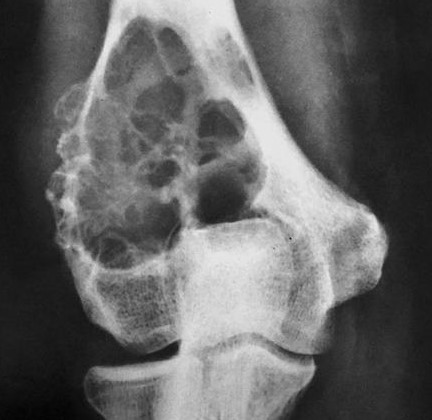

Рак Костей Симптомы И Проявление Фото

Рак Костей Симптомы И Проявление Фото 115 фото